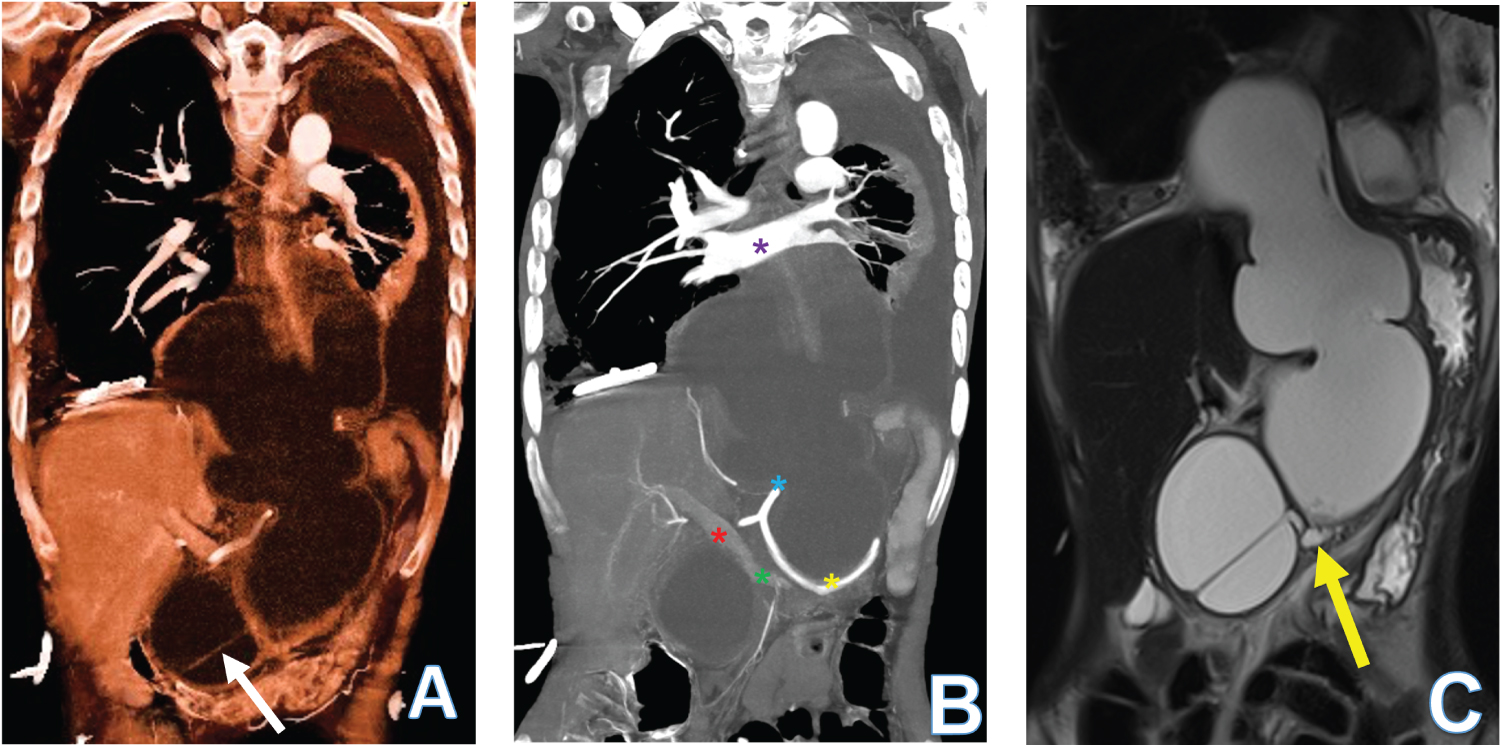

A 38-year-old female with a history of pancreatitis presented with breathing difficulties and tested positive for COVID-19. A CT of her chest, abdomen and pelvis with contrast showed a 8.5 × 13.1 × 25.4 cm (AP × ML × CC) multilobulated abdominal cyst extending into the posterior mediastinum with bilateral pleural effusion (Figure 1A). CT scan MipPR reconstruction showed the relation of the pseudocyst with abdominal and thoracic vessels (Figure 1B). Magnetic resonance cholangiopancreatography (MRCP) showed communication between the pseudocyst and the main pancreatic duct (Figure 1C). Esophagogastroduodenoscopy (EGD) with EUS confirmed a pancreatic pseudocyst through elevated amylase levels, and subsequent cystogastrostomy and cystoduodenostomy reduced the cyst [1]. A pancreatic pseudocyst is a complication of acute and chronic pancreatitis in which pancreatic secretions are found enclosed in a fibrous membrane [2]. While management of the patient was complicated by COVID-19 as a comorbidity, the pseudocyst was successfully treated through an endoscopic approach.

Figure 1: 38-year-old woman presenting with COVID-19 and a large pancreatic pseudocyst. (A) 3D reconstruction volume rendering using CT abdomen liquid algorithm shows a large, encysted fluid collection with septation. The epicenter is in the abdomen and extends into the posterior mediastinum primarily behind the left lung and bronchial tree. The pancreas is not seen separately; (B) CT scan 3D reconstruction using MipPR shows the relation of the pseudocyst with the celiac trunk (blue star), splenic artery (yellow star), main portal vein (red star), splenic vein (green star) and the pulmonary veins (purple star); (C) The MRCP study HASTE coronal image shows communication between the large cyst and the main pancreatic duct (yellow arrow).